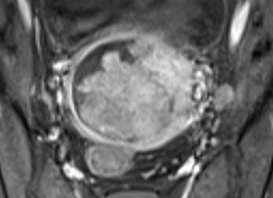

3. Ca thứ ba: Thất phải hai đường ra

Thai nhi 24 tuần 2 ngày. Hình ảnh siêu âm như sau:

Hình 6: Thất phải (TP) hai đường ra với động mạch chủ và động mạch phổi song song. Hai đại động mạch đều xuất phát từ thất phải, động mạch chủ phía trước và bên phải so với động mạch phổi. Động mạch phổi nhỏ so với động mạch chủ (hẹp động mạch phổi).

Hình 7: Thông liên thất (TLT) dưới động mạch chủ (ĐMC) trên siêu âm Doppler màu. Chú ý rằng động mạch chủ chủ yếu xuất phát từ thất phải.